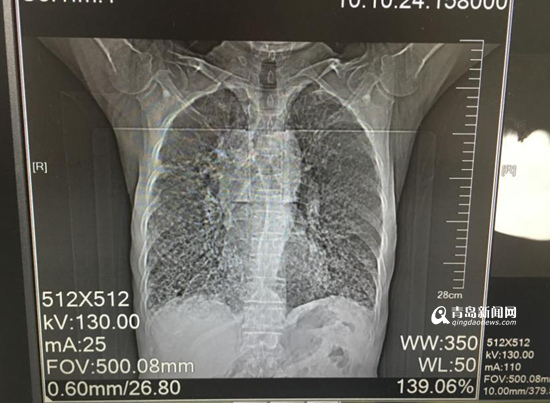

胸部CT顯示病灶彌漫。

根據(jù)患者病情、影像學(xué)檢查結(jié)果,經(jīng)集團(tuán)本部肺部感染診療中心主任兼西院區(qū)呼吸內(nèi)科學(xué)科負(fù)責(zé)人、首席專家劉學(xué)東主任與西院區(qū)呼吸內(nèi)科蘭淑娟主任及專家團(tuán)隊(duì)共同研究、探討,老人被確診為“彌漫性泛細(xì)支氣管炎”(簡(jiǎn)稱“DPB”)。呼吸內(nèi)科蘭淑娟主任說:“DPB通常在40歲左右起病,初期有慢性咳嗽和膿痰,后期則表現(xiàn)為活動(dòng)后呼吸困難且呈進(jìn)行性加重。臨床診斷標(biāo)準(zhǔn)包括必須項(xiàng)目項(xiàng)及參考項(xiàng)目?!北仨氻?xiàng)目三項(xiàng),分別是:持續(xù)咳嗽、咳痰及勞力性呼吸困難;目前或過去有鼻竇炎;胸部X線示兩肺彌漫性散在分布的顆粒樣結(jié)節(jié)狀陰影或胸部CT示兩肺彌漫性小葉中心性顆粒樣結(jié)節(jié)狀陰影。參考項(xiàng)目三項(xiàng),分別是:肺部可聞及啰音;FEV1/FVC<70%,PO2<80mmhg;冷凝集>=1:64。

蘭淑娟主任表示:“該患者除癥狀符合描述,還曾因慢性鼻竇炎看過多年病。患者具有典型的影像學(xué)表現(xiàn),符合DPB臨床診斷標(biāo)準(zhǔn)?!?/p>